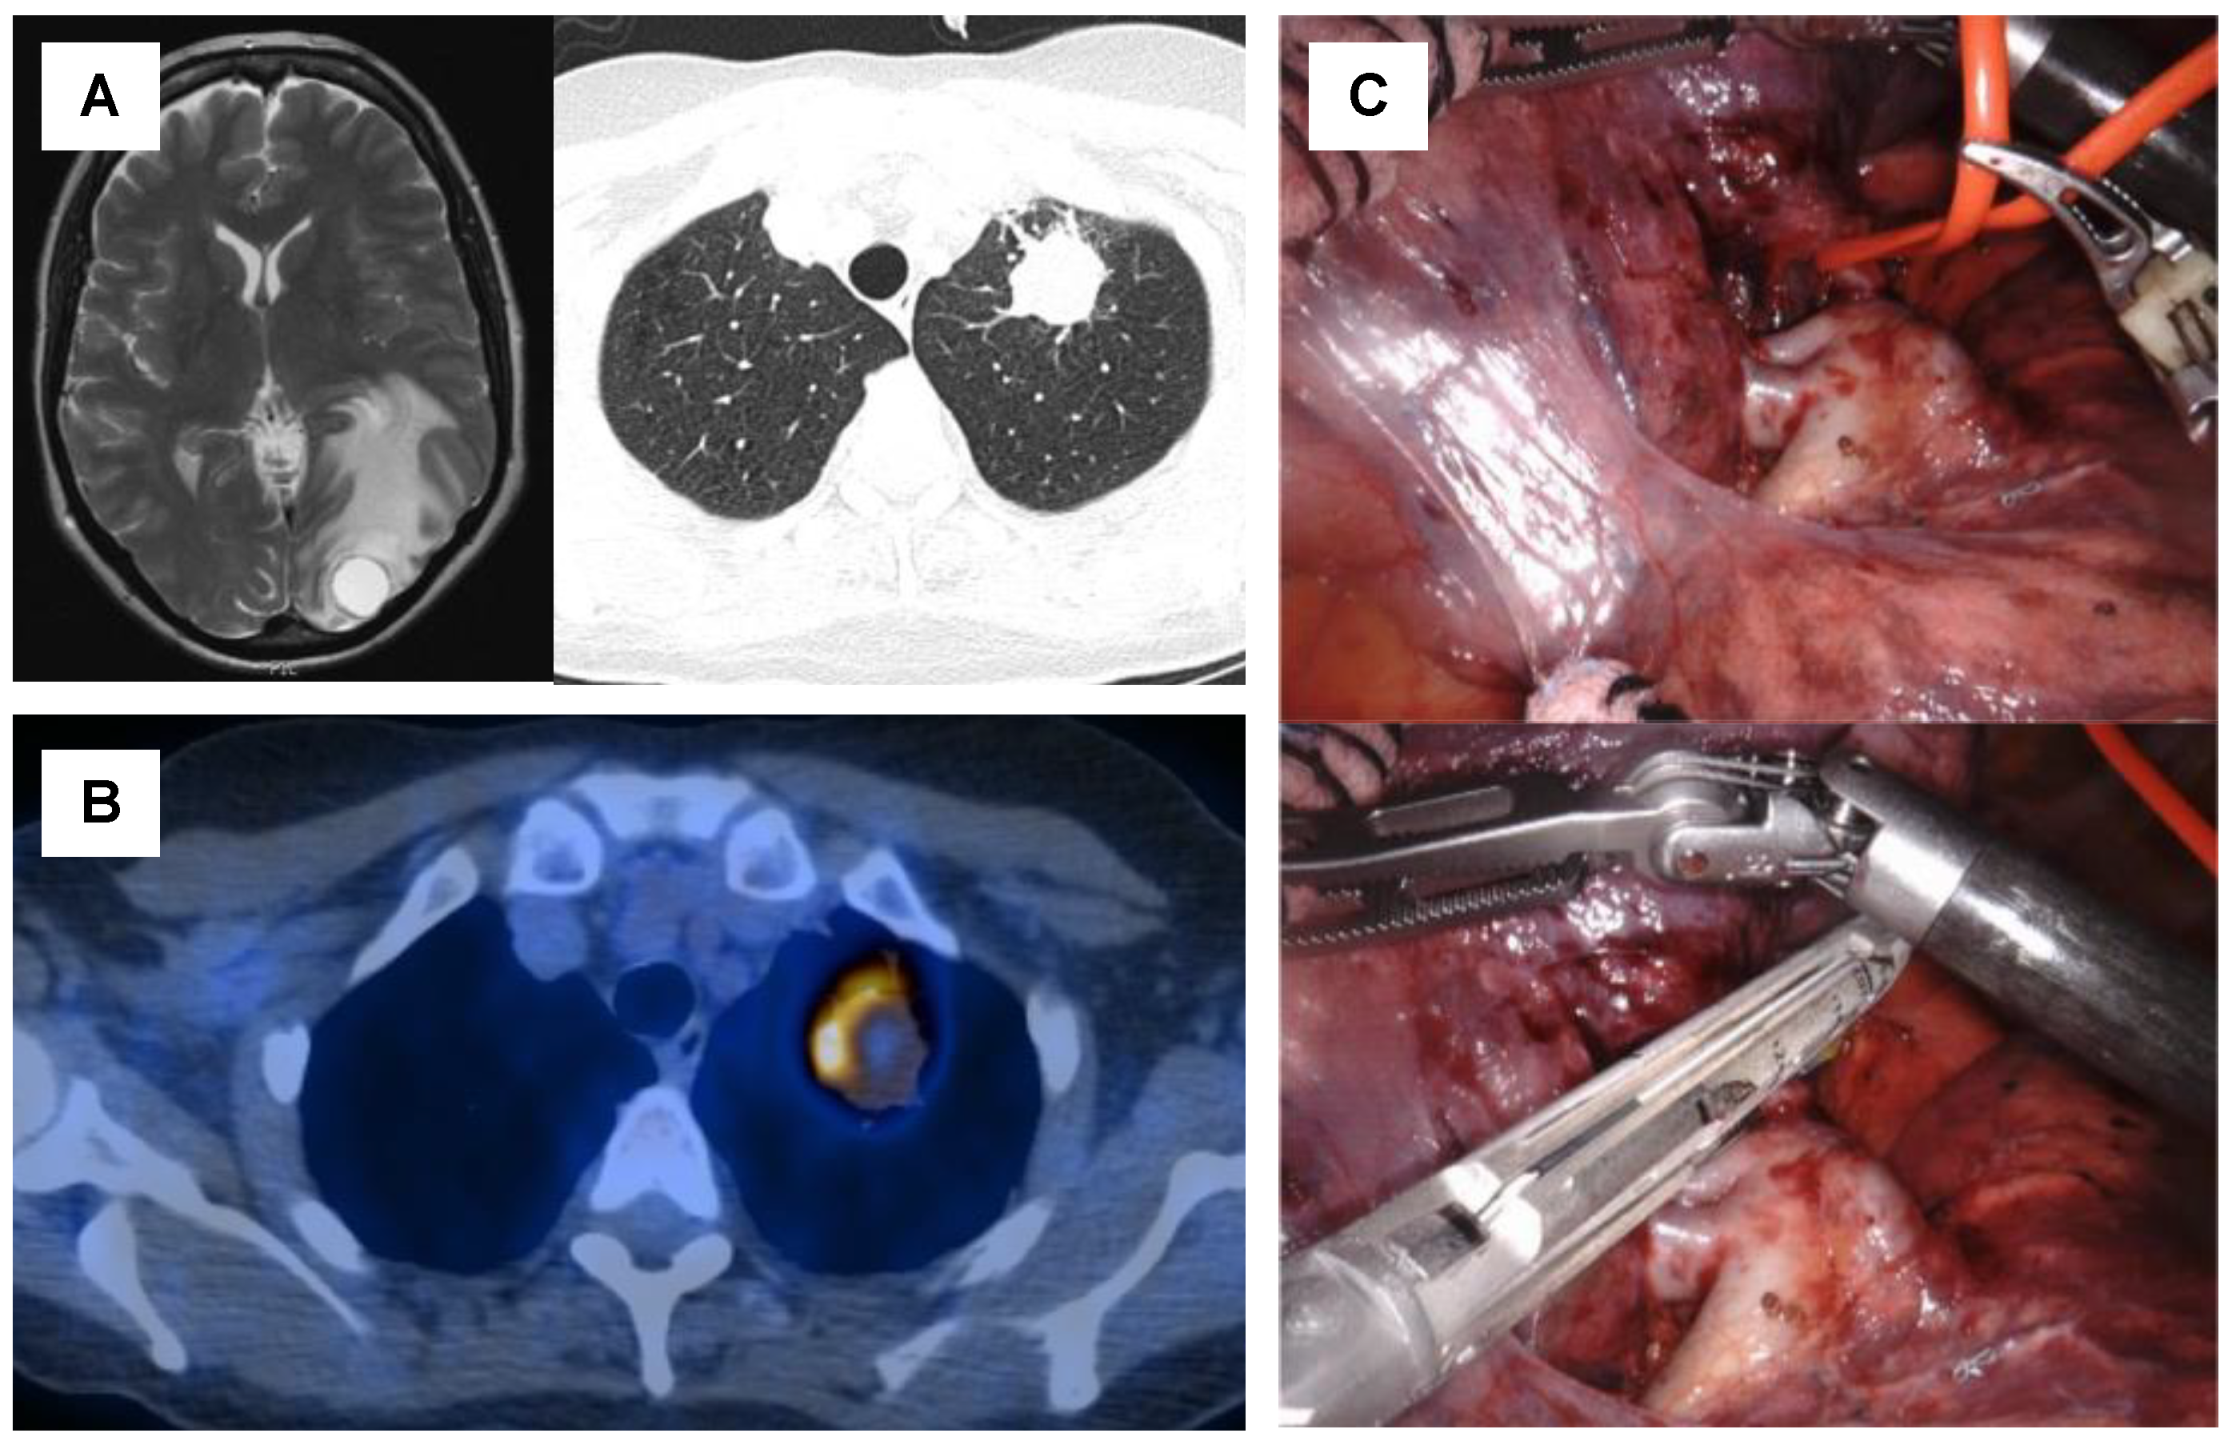

- Curioni-Fontecedro, A.; Ickenberg, C.; Franzen, D.; Rogler, G.; Burger, I.A.; Broek, M.V.D. Diffuse pseudoprogression in a patient with metastatic non-small-cell lung cancer treated with Nivolumab. Ann. Oncol. 2017, 28, 2040–2041. [Google Scholar] [CrossRef] [PubMed]